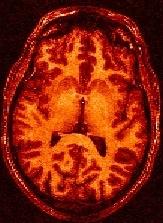

You may think that a unequivocal correspondence exists between the grey level in one voxel of a T1-weighted MR scan, and some esoteric property of the underlying cube of tissue. You should not succumb to this temptation. Take some time to observe a standard anatomical scan with a rainbow colormap to have this revelation:

Some parts of the white matter are red, while some others are yellow or even green. All looks like as if the putative correspondence mentioned above was depending on the localization in the field of view. Usually, the center of the coil is lighter, but this is not a systematic observation and depends on the coil and scanner design. When one looks at a MR slice with a grey colormap, like in standard radiology, this default is not straightforward. Human vision, indeed, is very effective at correcting for this kind of spatial variations. This capacity has some link with the fact that we usually perceive object's colors as uniform, whatever illumination related variations. Unfortunately, this sophisticated feature of human vision has prevented the MR physicists to find the motivation to overcome that acquisition problem. Artificial vision still being in its infancy, it is much more disturbed by these spatial intensity variations than radiologists. This procedure has to correct for the spatial bias before any segmentation process can be reliably trigered.